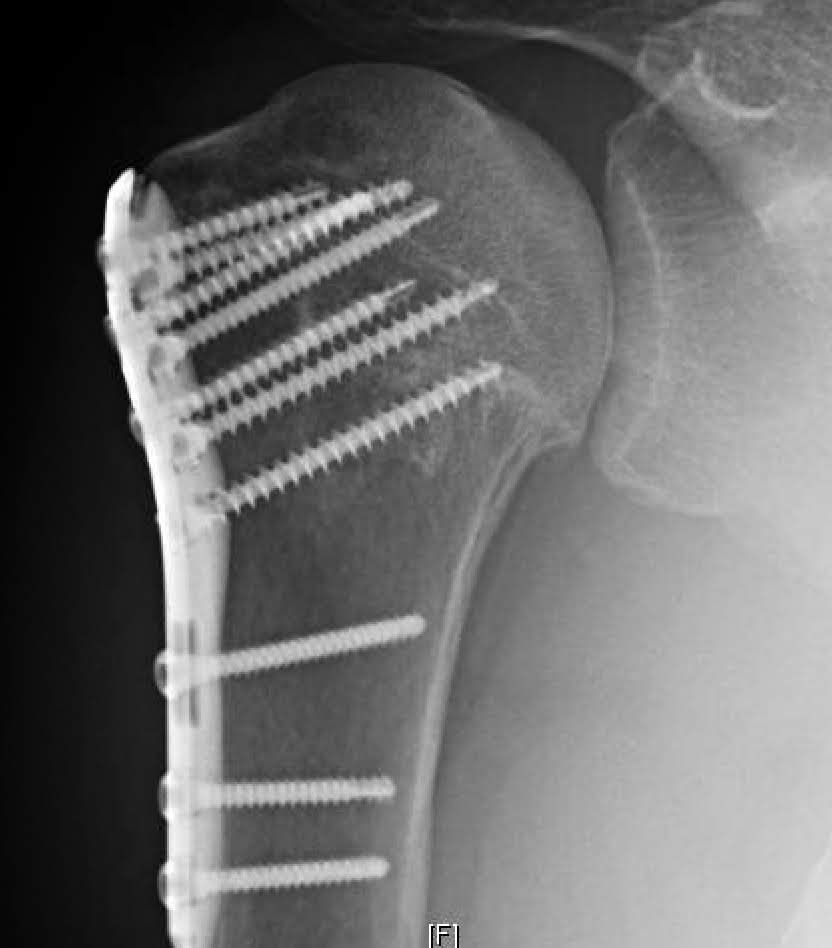

From shoulderarthritis.blogspot.com

UW Shoulder and Elbow Academy Post traumatic arthritis of the shoulder, xray appearance Arthritis From Trauma Pta causes about 12% of all osteoarthritis cases, and a history of physical trauma may also be found in. In severe cases, it can also tear the cartilage from bone resulting in cartilage loss and eventual joint degeneration. Advice to improve your movement, fitness, and overall health from. Learn more about how post traumatic arthritis develops, how common it is,. Arthritis From Trauma.